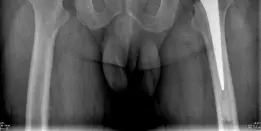

* الأشعة السينية (X-rays): هي الفحص الأول والأكثر أهمية. تظهر الأشعة السينية علامات مميزة للفُصال العظمي مثل:

* تضيق المسافة المفصلية: يظهر المفصل ضيقًا بسبب تآكل الغضروف.

* تكون النتوءات العظمية (Osteophytes): نتوءات عظمية صغيرة تتشكل حول حواف المفصل.

* تصلب تحت الغضروف (Subchondral Sclerosis): زيادة كثافة العظم تحت الغضروف التالف.

* تكيسات تحت الغضروف (Subchondral Cysts): جيوب صغيرة مملوءة بالسوائل تتشكل في العظم.

* تشوه رأس الفخذ: قد يفقد رأس الفخذ شكله الكروي الطبيعي.

صورة الأشعة السينية قبل العملية تظهر التهابًا حادًا في مفصل الورك الثنائي مع تضيق في المسافة المفصلية، نتوءات عظمية، وتغيرات تحت الغضروف.

الشكل 1: صورة الأشعة السينية قبل العملية تظهر التهابًا حادًا في مفصل الورك الثنائي مع تضيق في المسافة المفصلية، نتوءات عظمية، وتغيرات تحت الغضروف.